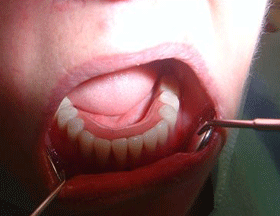

This picture shows the bottom view of the denture with anchoring slots clearly visible.

This picture shows removable dentures securely anchored onto metal support bar.

Great advantage of this type of denture is that it always stays securely in place and in that way eliminates embarrasing situations where conventional dentures may suddenly “pop out” during the meal or in the middle of the sentence.